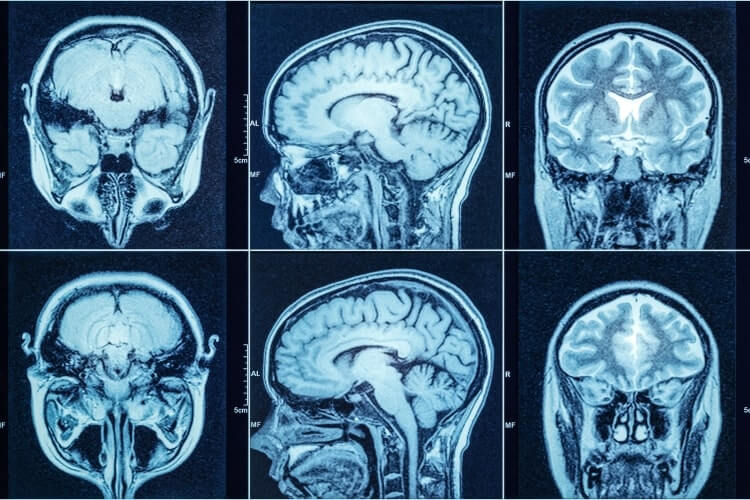

V posledních letech, se zvyšujícími se znalostmi etiopatogeneze a s lepšími paraklinickými vyšetřovacími metodami, došlo k úpravě klinického popisu progresivní MS. Cílem je totiž zahájit terapii v co nejčasnější fázi onemocnění, kdy dominují zánětlivé procesy. Byly proto definovány tzv. modifikátory průběhu MS, které ukazují na to, zda je ještě přítomen zánětlivý potenciál. Prvním je aktivita onemocnění, která je definována relapsem či přítomností nové léze na magnetické rezonanci (MR). Druhým je progrese, hodnocená pomocí klinického vyšetření. Kombinacemi těchto modifikátorů lze popsat čtyři fenotypy progresivní MS: aktivní s progresí/bez progrese a neaktivní s progresí/bez progrese (Lublin FD et al., Neurology 2014). „Toto rozdělení má svůj klinický význam, protože jak víme z klinických studií, na terapii nejlépe odpovídají pacienti se zachovanou zánětlivou aktivitou. Na druhou stranu pro nemocné s neaktivní chorobou pak budou určeny jen léky neuroprotektivní,“ vysvětluje D. Horáková.

„Abychom si mohli odpovědět na otázku, zda má zařazení do subtypu praktický, či léčebný význam, musíme se podívat na nové poznatky o imunopatogenezi, které se v posledních letech velmi posunuly. Ty mají svůj praktický význam – říkají nám totiž, jaké léky bychom měli používat a jaké bychom potřebovali,“ podotýká D. Horáková. Lassmann H et al. na základě vlastního dlouhodobého výzkumu popsali a publikovali patogenetické procesy jednotlivých fází MS. V časném stadiu zánět začíná v periferii a ve vlnách vstupuje do centrálního nervového systému, je otevřená hematoencefalická bariéra, takže je na MR často viditelný enhancement gadolinia a objevují se nové fokální léze, zejména v bílé hmotě.

V pozdní, progresivní fázi, dochází ke změně charakteru zánětu. Lymfocyty setrvávají v centrálním nervovém systému a postupuje difuzní poškození bílé i šedé hmoty. Probíhá kortikální demyelinizace s výrazným postižením kortexu a tvorbou tzv. sekundárních germinálních center a dochází k pozvolné progresi již dříve vzniklých lézí. Uzavírá se hematoencefalická bariéra, za kterou se vytváří kompartment zánětu. „V tuto chvíli si zánět začíná žít vlastním životem a problém je, že většina dostupných léků se přes uzavřenou hematoencefalickou bariéru není schopna dostat,“ dodává D. Horáková.